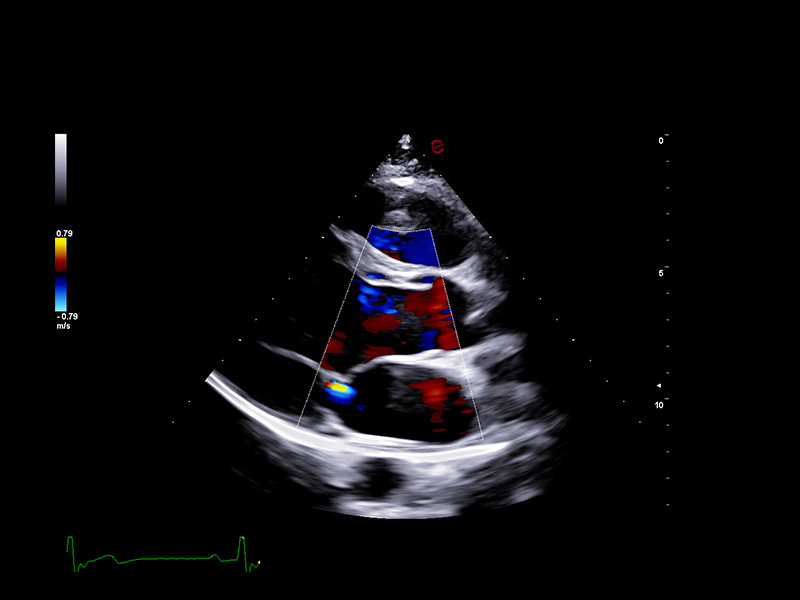

Innovative hemodynamic assessment with HyperDoppler

Esaote’s HyperDoppler technology provides an advanced visualization of intracardiac blood flow dynamics, offering clinicians an intuitive understanding of complex hemodynamics that goes beyond conventional Doppler imaging. By generating real-time vector maps, streamlines, and vortex formations, HyperDoppler enables the detailed assessment of diastolic function, ventricular dyssynchrony, and valvular abnormalities.

This unique flow visualization supports earlier detection of subtle dysfunction, particularly in challenging cases such as heart failure, prosthetic valve evaluation, and structural heart disease. HyperDoppler’s zero-click, visually rich interface enables faster, more comprehensive exams, allowing cardiologists to make more informed clinical decisions.